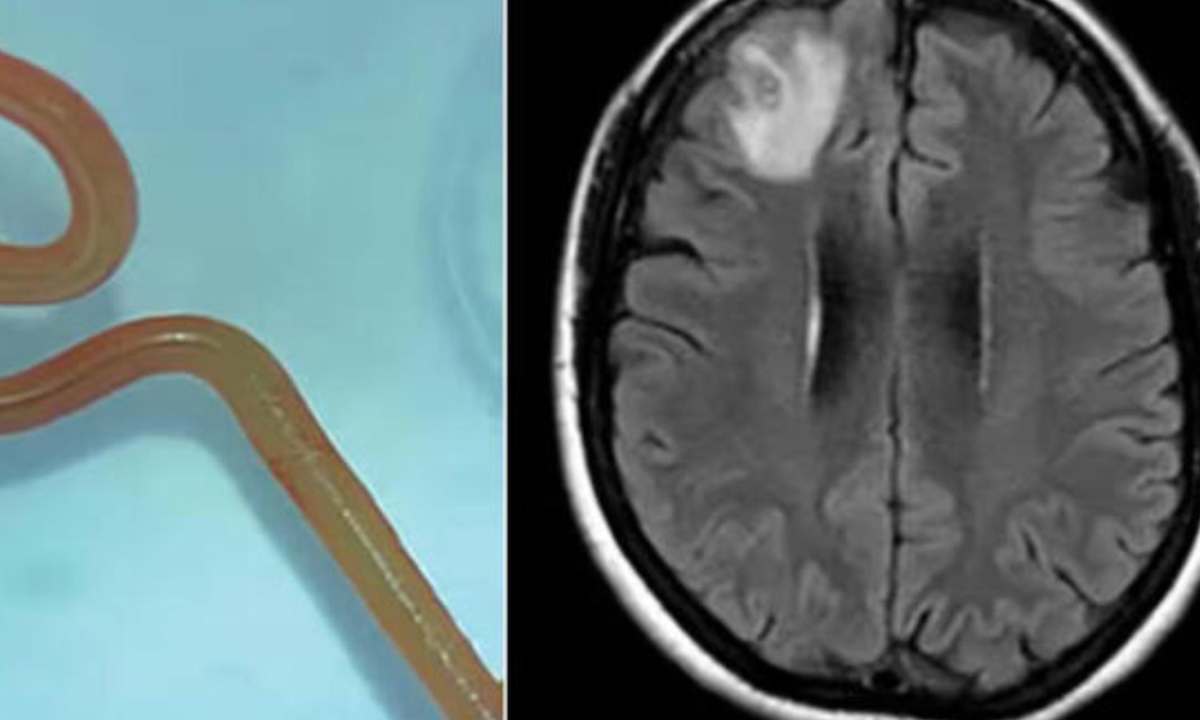

Ma un esame piรน approfondito ha portato alla scoperta di un granuloma che, una volta estratto, ha rivelato qualcosa di ancora piรน sorprendente. Si trattava di una tenia di 25 centimetri che premeva sui nervi e da qui le terribili convulsioni. Ma com’รจ possibile che una tenia si formi nel cervello? In alcuni, rarissimi casi, puรฒ accadere. La colpa probabilmente รจ dell’abuso di carne poco cotta con molti ingredienti aromatizzanti, cosa che ha portato allo sviluppo di questo lunghissimo verme.